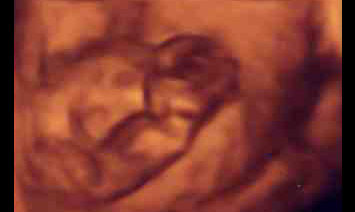

矢内原医院「4D」写真

お腹の中の「私」が見える?左は、9週目の「私」。右は29週になった「私」。最新型の「4D」というマシンを使って撮った写真です。でも特...